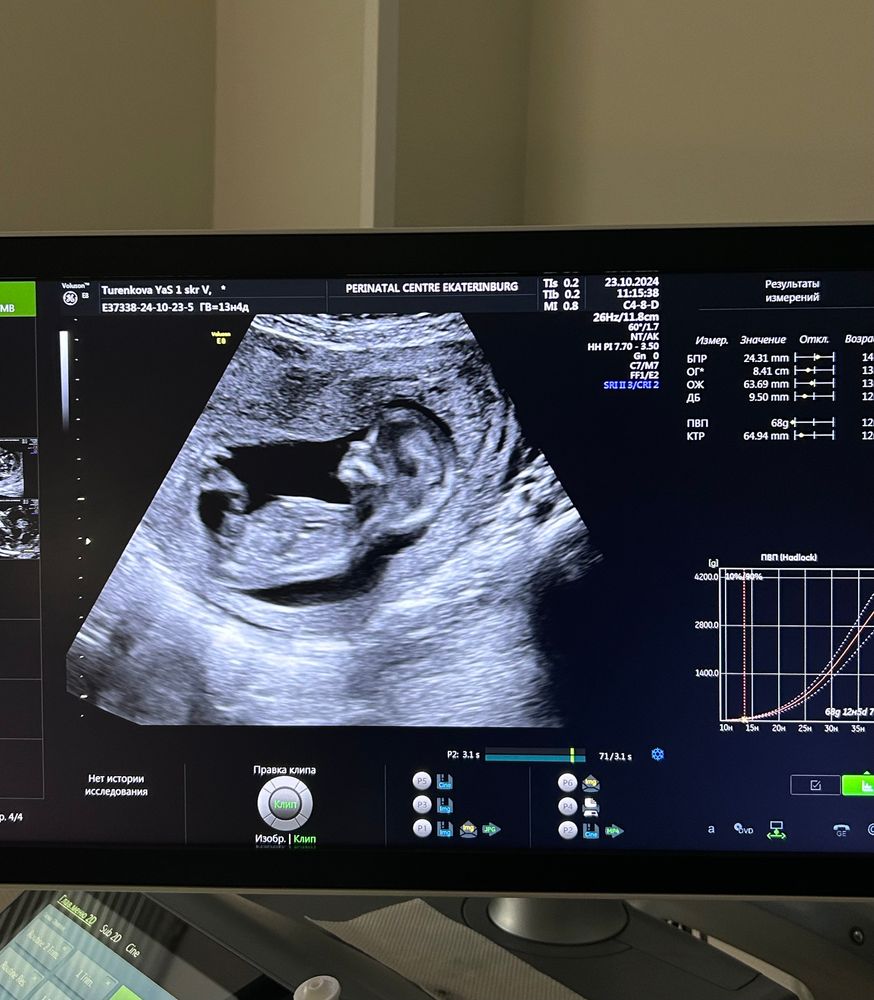

1 скрининг пройден! 🥳

Анастасия, сейчас смотрю значения бпр аж на 14 недель и окружность головы на 13,5

Яна , это все индивидуально и оценивает только узист. Все эти таблицы в интернете это фигня. Я даже не смотрела. Мне было достаточно что врач сказал, что малыш хороший